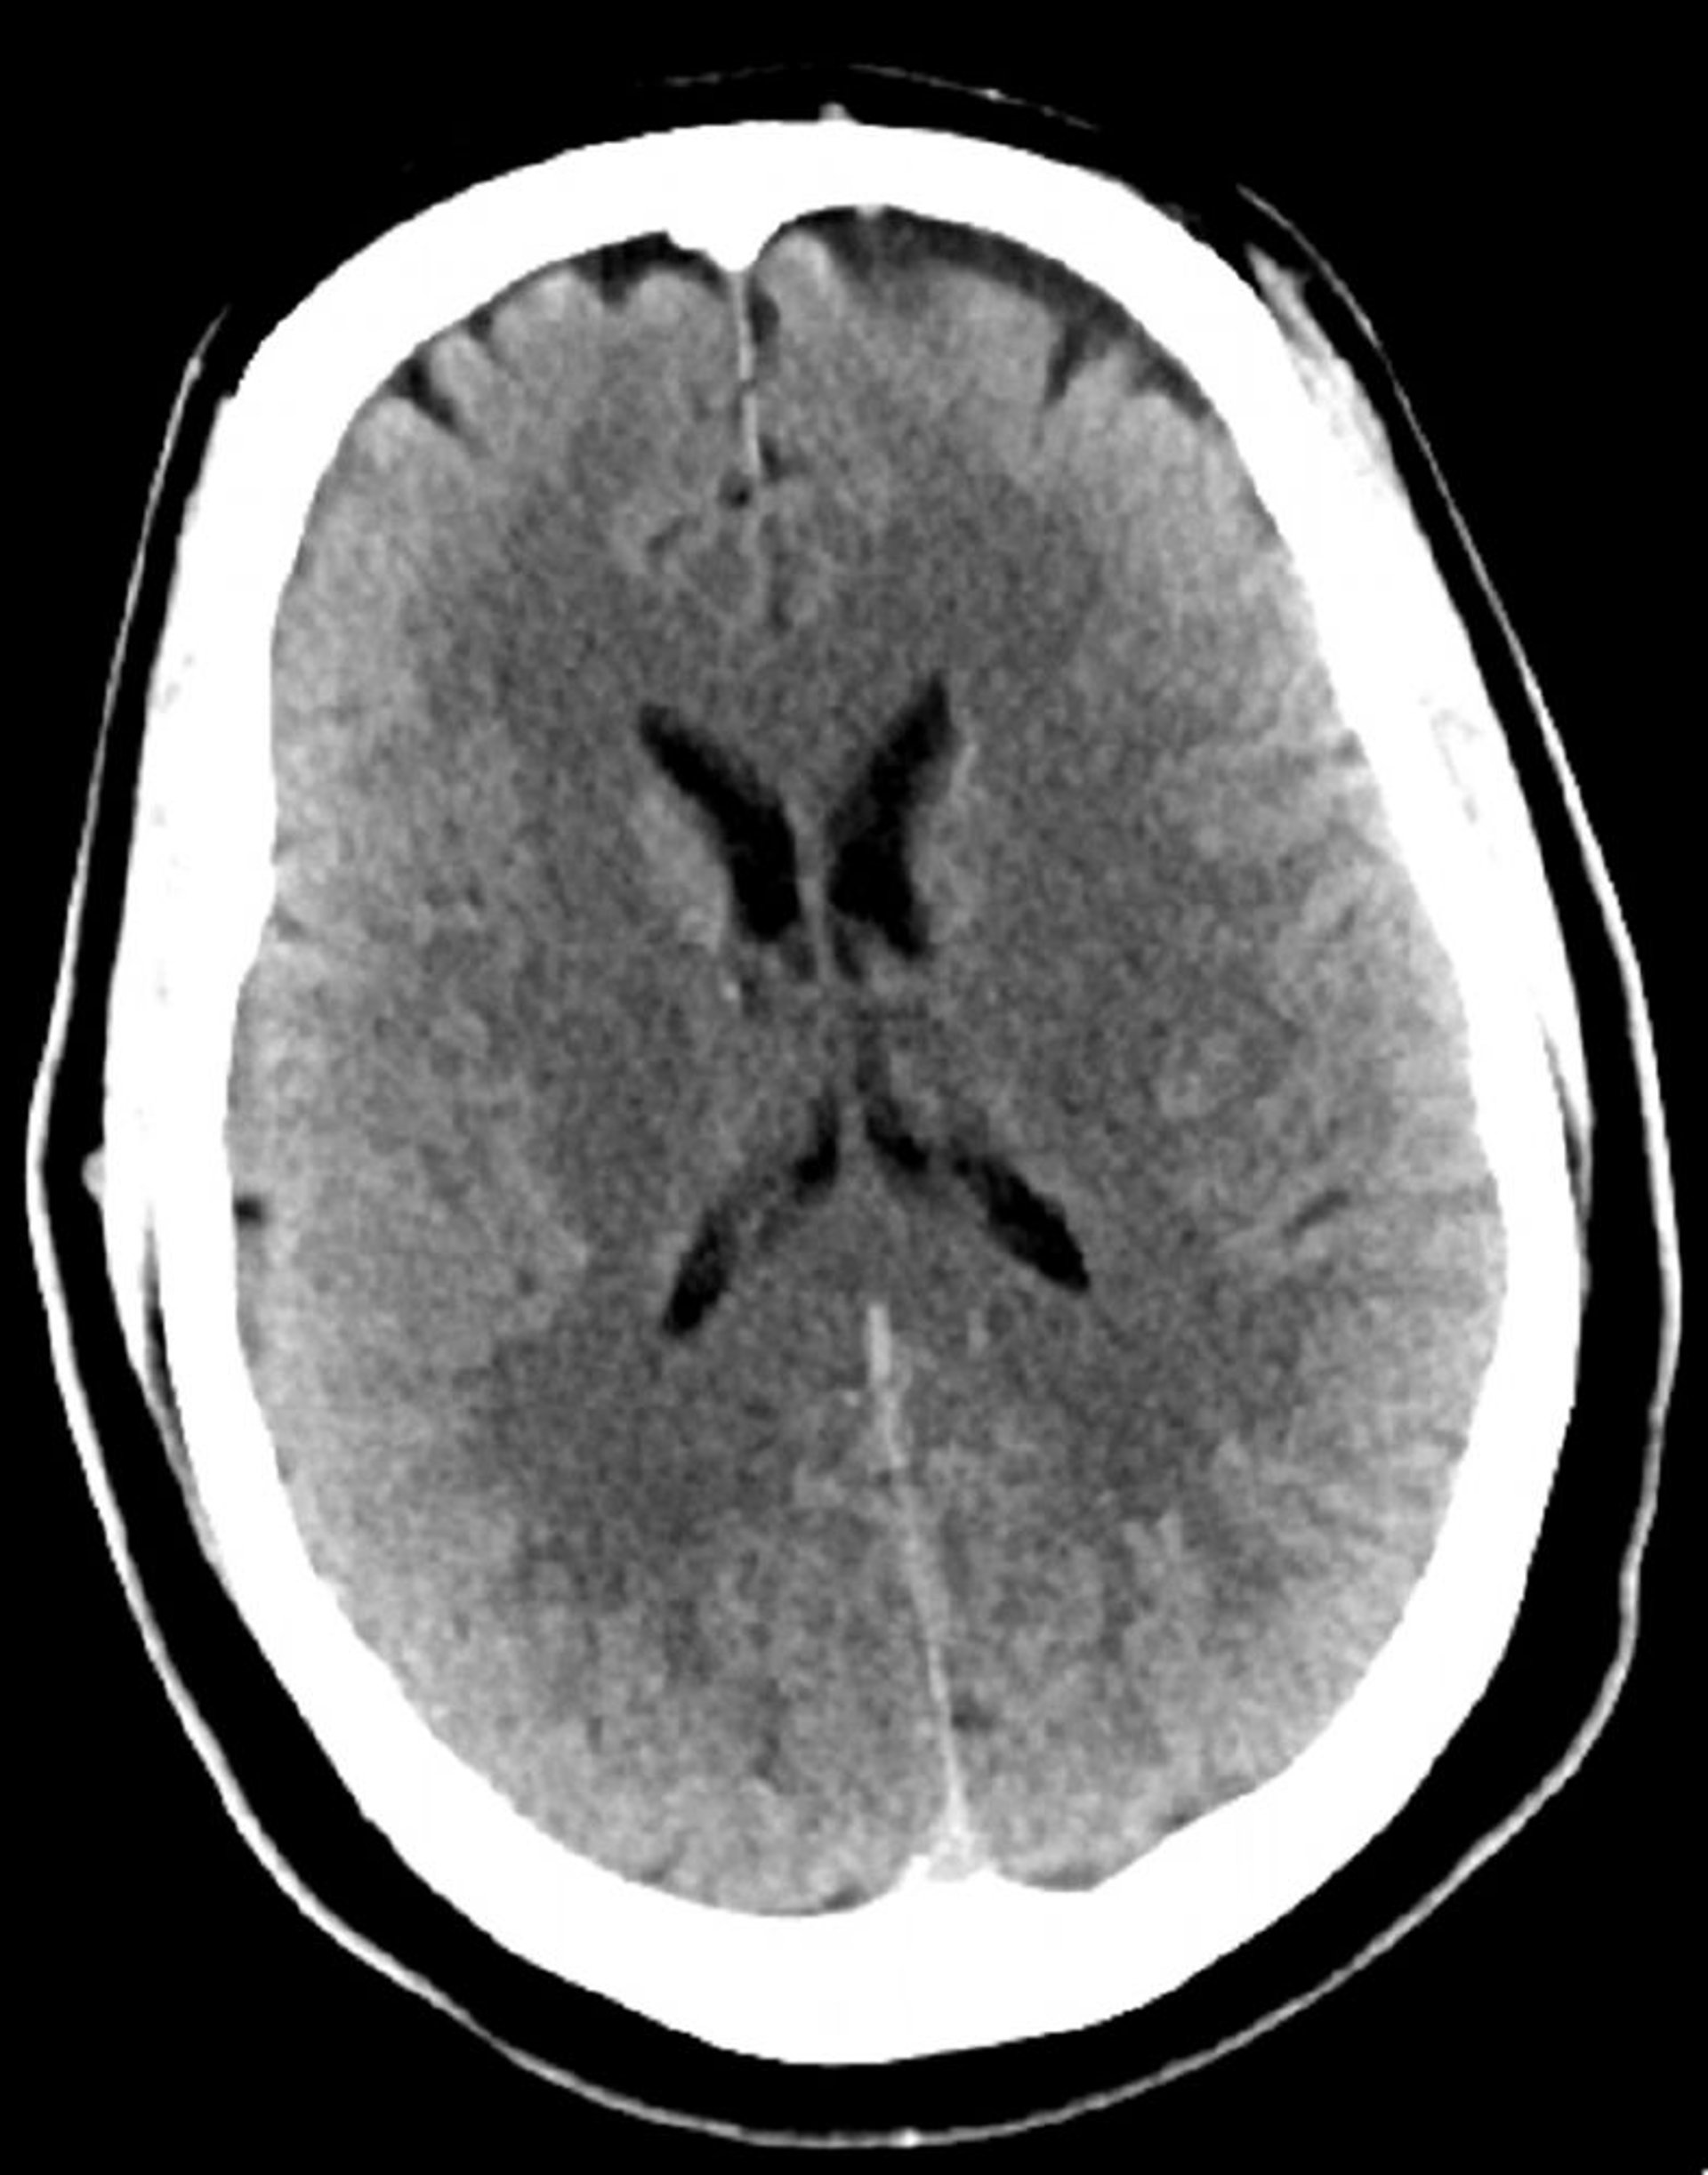

Tomodensitométrie normale de la tête (adulte 30 ans) – Diapositive 4

Cette image est une TDM normale de la tête d'un jeune adulte âgé de 30 ans. Il n'y a pas de liquide intra- ou extra-axial ou d'hémorragie. La différenciation gris-blanc est préservée. La taille du ventricule et la forme des sillons semblent normales.